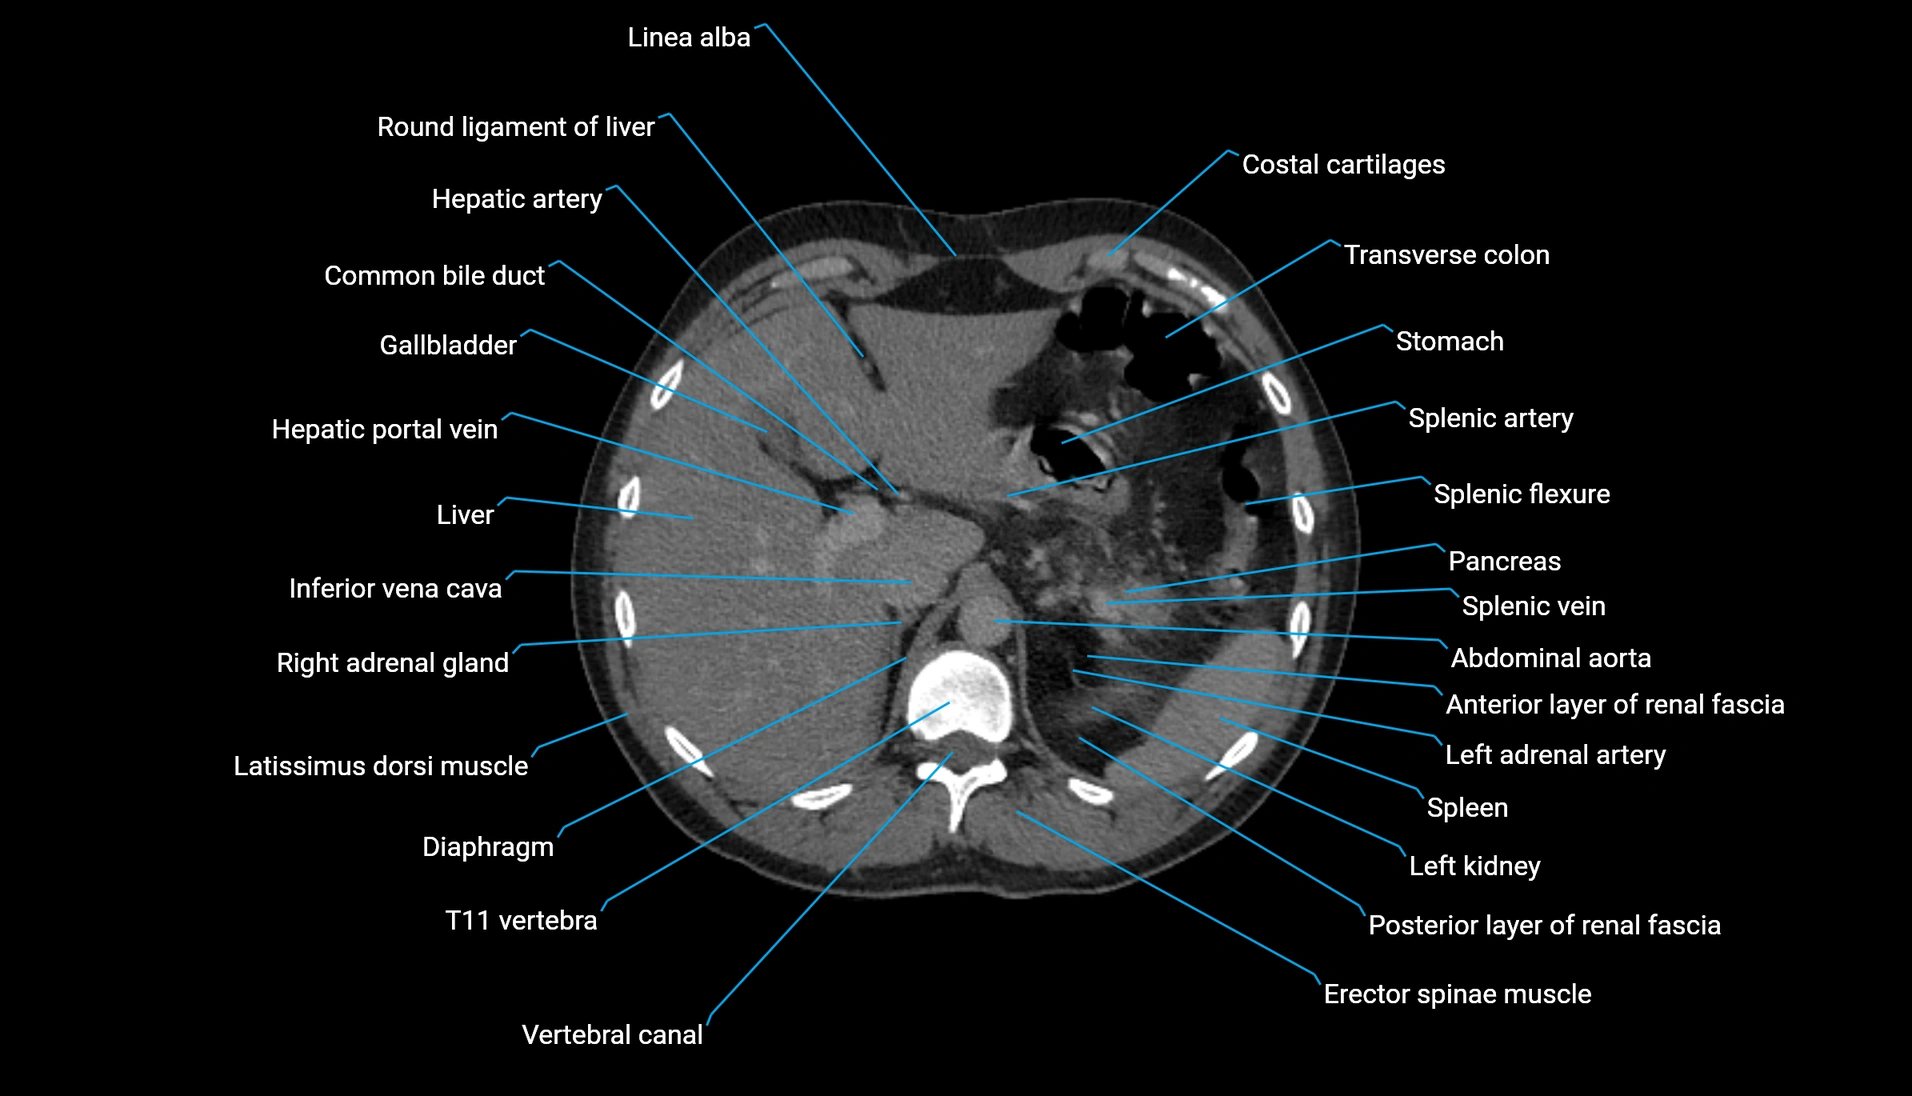

CT Appearance

Non-contrast CT:

-

Demonstrates cortical bone of acetabular rim in excellent detail

Detects fractures, dysplasia, retroversion, or bony overcoverage (pincer impingement)

3D reconstructions used in preoperative hip surgery planning

CT VRT 3D image

CT image